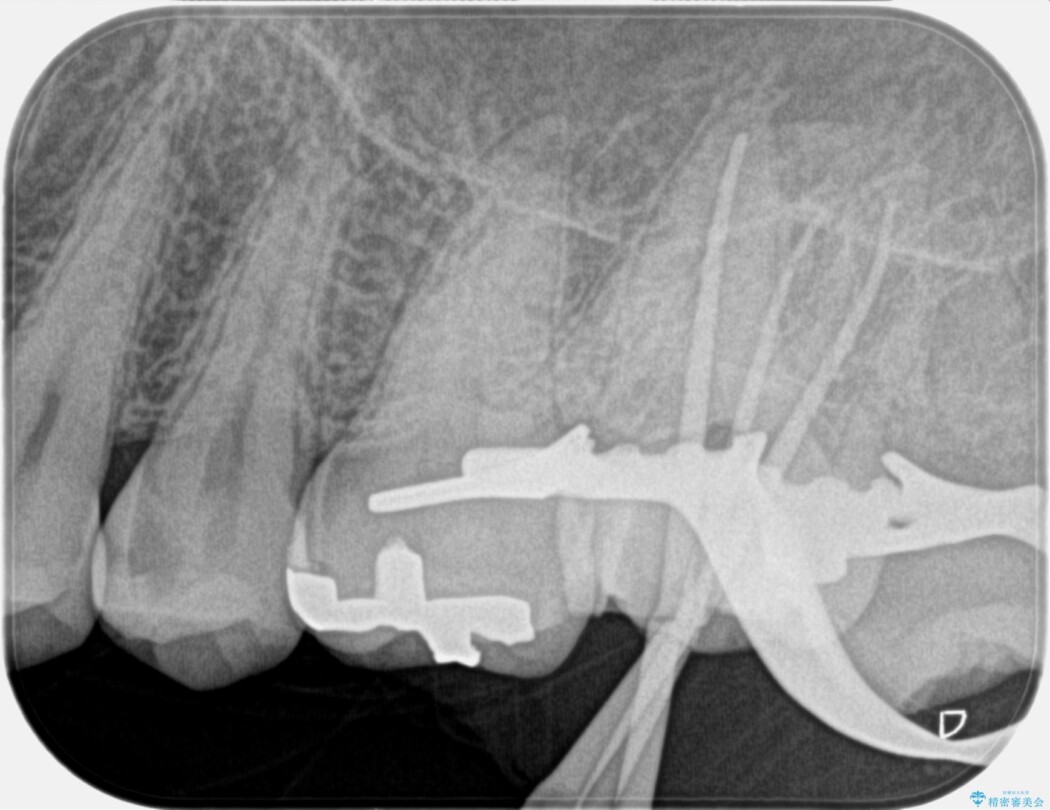

詳しく検査をしたところ、虫歯が深く歯髄の保存が出来ない状態と判断しました。

よってまずは根管治療を行って感染した神経を取り除き、セラミッククラウンで修復をすることとしました。